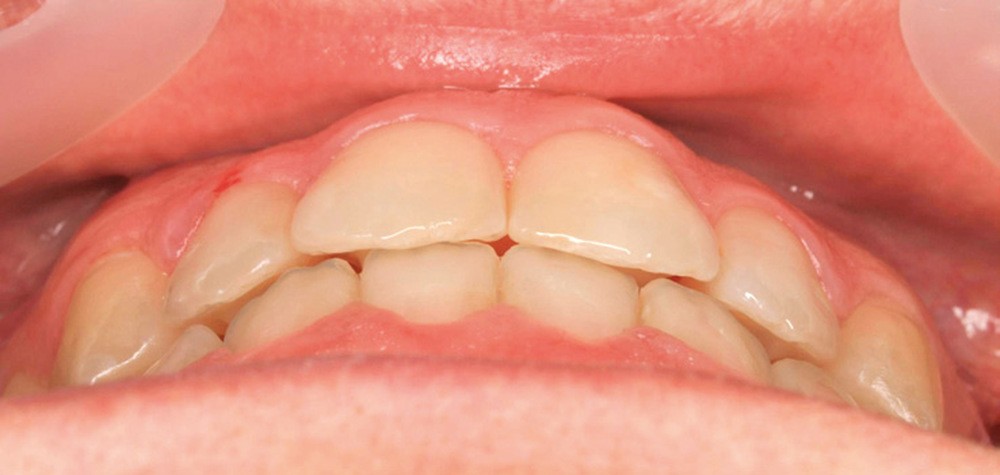

Diagnostic (fig. 1a-g)

La patiente présente une classe III squelettique dans un contexte hyperdivergent associée à une endoalvéolie maxillaire, un articulé inversé antérieur, une rétroversion incisive maxillaire, des rapports de classe I canine bilatérale, une absence de 16 et 36.

Au niveau esthétique, le profil est rectiligne. La lèvre supérieure est plus effacée, en retrait par rapport à la lèvre inférieure. De face et de profil, la mandibule paraît massive et le maxillaire effacé : le manque de soutien de la lèvre supérieure contribue à cette impression.

Le sourire est étroit, dégradé par les malpositions dentaires.

Au niveau fonctionnel, il existe un pro-glissement mandibulaire et un articulé inversé antérieur. Le profil téléradiographique montre en occlusion des rapports labiaux et un profil de classe III plus marqué que sur photographies.